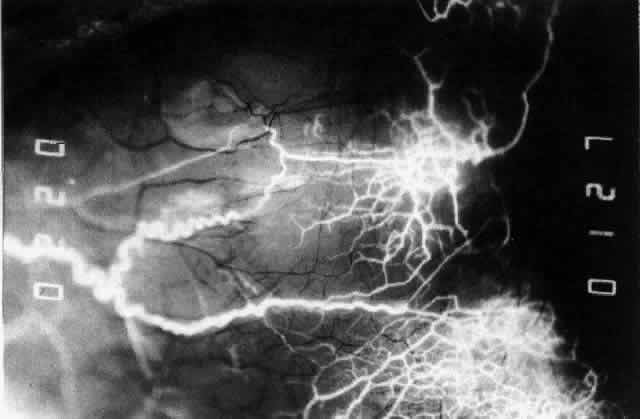

The characteristic features of necrotizing scleritis on fluorescein angiography

are hypoperfusion and, eventually, nonperfusion of the vascular

networks (Figs. 40 through 43).26 The initial changes are on the venous side of the capillary network; the

transit time of the dye increases even if the eye is red and congested. If

the disease process persists or has been present for a long time, thrombosis

and permanent vaso-occlusive changes occur. These vessels (or

the occluded capillary network) are bypassed by the opening of

anastomotic channels. New vessels in a granuloma give rise to deep intrascleral

leakage of dye (see Fig. 43). Conjunctival and episcleral involvement by the destructive change is

Fig. 43. Late venous phase of angiogram of a patient with necrotizing scleritis

showing late deep leakage from vessels on the surface of the sclera and

leakage of the capillary network at the limbus and the vessels draining

it, together with poor or absent perfusion of the remaining vessels. Fig. 43. Late venous phase of angiogram of a patient with necrotizing scleritis

showing late deep leakage from vessels on the surface of the sclera and

leakage of the capillary network at the limbus and the vessels draining

it, together with poor or absent perfusion of the remaining vessels.

|